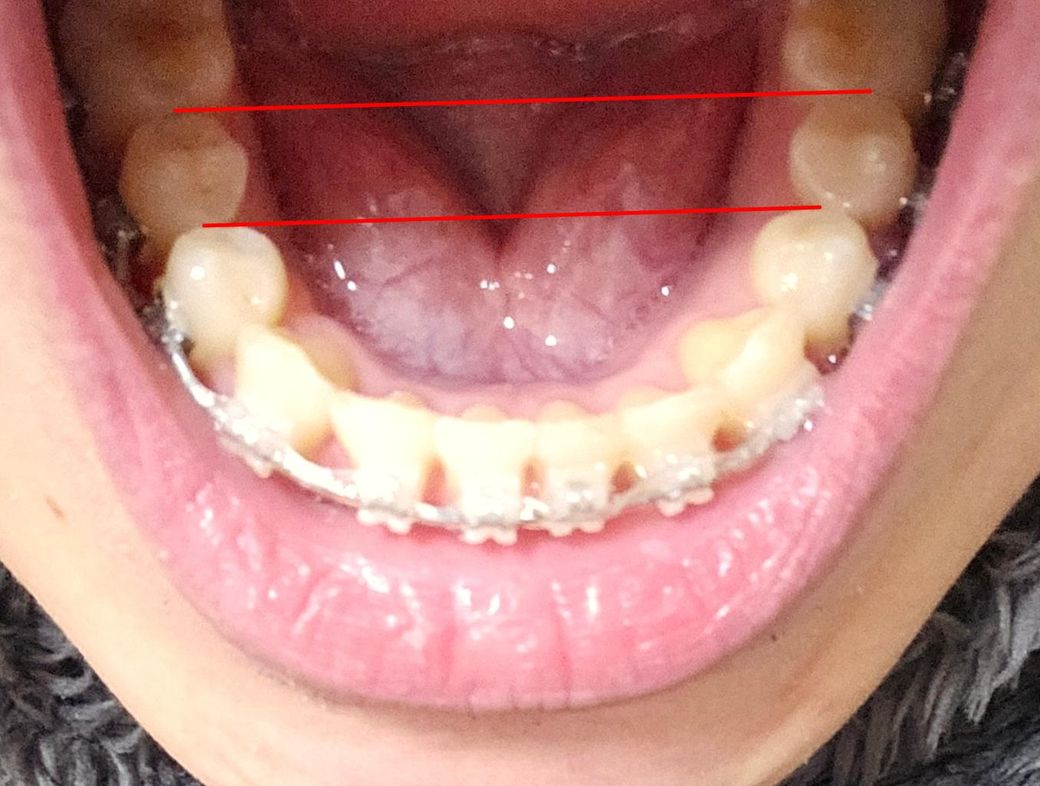

치아를 상하로도 교정할 수 있나요??

치아 교정중인데 사진을 보시면 양쪽의 높이(깊이)가 다르다는 걸 알 수 있는데요.

• 1번 째 사진

1.사진으로 봐서 양쪽 작은 어금니의 높낮이가 다른지는 명확히 파악되진 않습니다

1. 높낮이가 다르다면 아마 한쪽이 덜물리고 반대쪽이 강하게 물릴 겁니다

2. 압하, 정출 교정 가능합니다